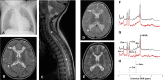

Methods and results: Here, we report the clinical and molecular investigations of two patients with histochemical and biochemical evidence of a severe, isolated complex II deficiency due to novel SDH gene mutations; the first patient presented with cardiomyopathy and leukodystrophy due to compound heterozygous p.Thr508Ile and p.Ser509Leu SDHA mutations, while the second patient presented with hypotonia and leukodystrophy with elevated brain succinate demonstrated by MR spectroscopy due to a novel, homozygous p.Asp48Val SDHB mutation. Western blotting and BN-PAGE studies confirmed decreased steady-state levels of the relevant SDH subunits and impairment of complex II assembly. Evidence from yeast complementation studies provided additional support for pathogenicity of the SDHB mutation.